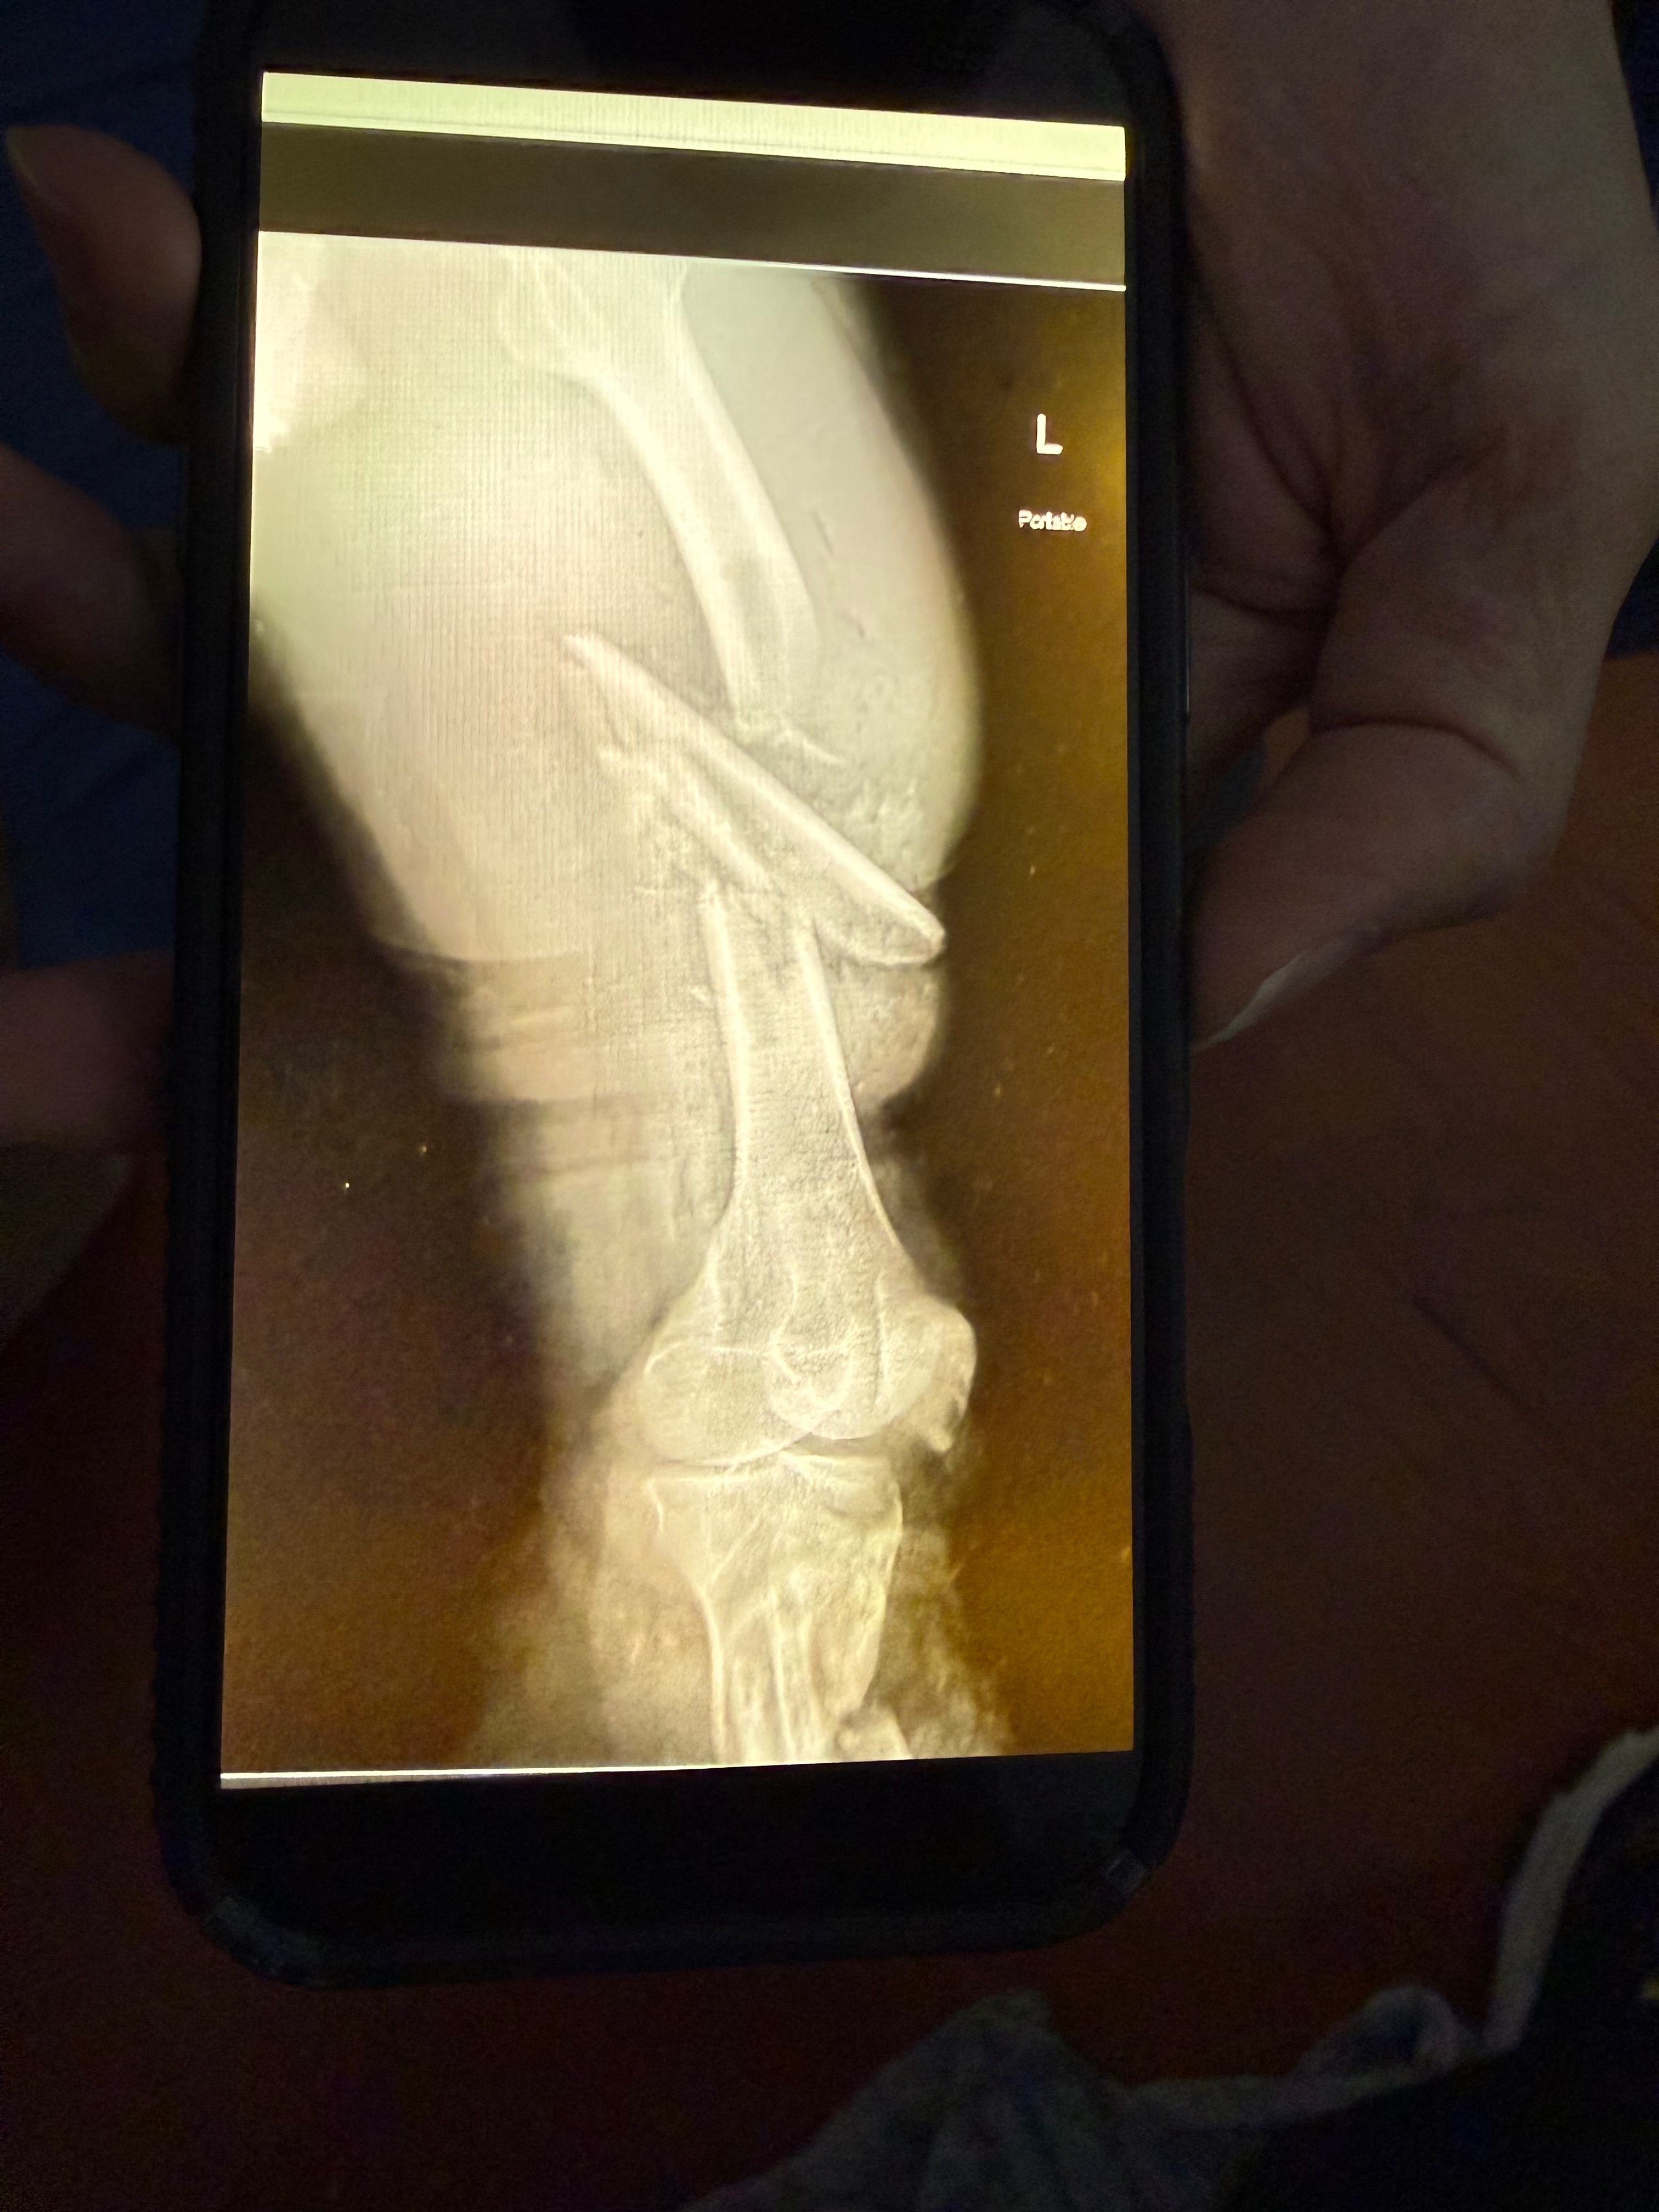

On October 5th, our dear friend Tony Day was in a devastating accident that changed his life in an instant. He suffered multiple severe injuries — including an above-the-knee amputation, collapsed lung, and fractures to his ribs, hips, and collarbone.